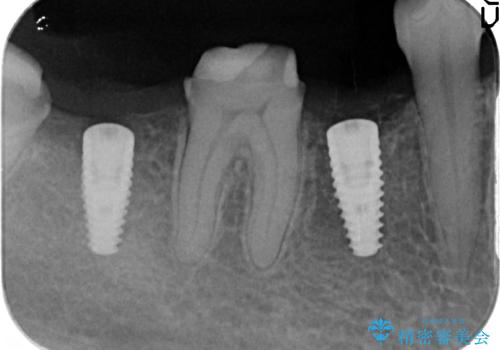

- 右下の奥歯の被せ物が外れてしまったので診て欲しいといらっしゃった方の症例です。

右下7は欠損しており、右下5は保存不可能だったため、インプラントによる欠損補綴を行いました。

インプラント埋入時には骨が不十分な部位に骨増生を行っております。